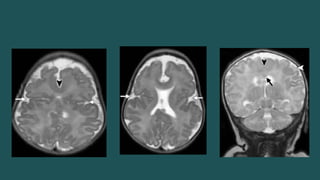

SEMILOBAR

Semilobar y Lobar El único hallazgo obvio por US a las 18-20 sdg sería la incapacidad de detectar el cavum septum pellucidum. • La malformación es semilobar si los lóbulos frontales están fusionados > 50%. • Hoz y fisura interhemisférica posterior y parte posterior del cuerpo calloso Hipotálamo y tálamo siempre fusionados SEMILOBAR

• #19 El diagnóstico prenatal de HPE alobar es bastante sencillo Semilobar y lobar pueden ser un desafío. In semilobar HPE, the interhemispheric fissure and falx cerebri may be present posteriorly and part of the corpus callosum may be seen in the region of the posteriorly sepa rated hemispheres , with the anterior extent corresponding to that of the interhemispheric fissure. somewhat arbitrary criterion used in postnatal imaging is that the malformation is semilobar if the frontal lobes are more than 50% fused

• #20 Semilobar HPE. (a) Axial oblique US image shows a continuous mantle of brain anteriorly (arrowheads) but posterior division into hemispheres (arrows). (b) More inferior axial US image in the same patient shows normal posterior fossa structures (arrow) below the tentorium but fused anterior supratentorial brain (arrowheads).

• #21 Semilobar HPE. (a) Coronal US image shows a monoventricle (*) and partial fusion of the thalami (T). (b) Coronal T2-weighted half-Fourier RARE MR image shows the continuous anterior brain parenchyma (arrow), monoventricle (*), and partially fused thalami (T). (c) Coronal T2-weighted half-Fourier RARE MR image more posteriorly shows two occipital lobes separated by the falx (arrow).